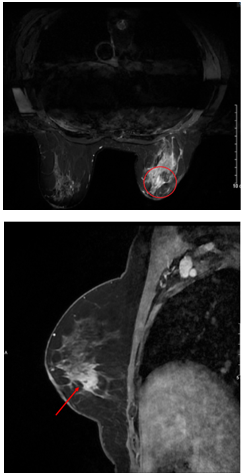

Hình 1. Hình ảnh X-quang tuyến vú: đám tăng đậm độ kèm vi vôi hóa vú góc 1/4 dưới ngoài vú phải (vòng tròn đỏ và mũi tên đỏ).

Hình ảnh MRI vú: Nhu mô góc 1/4 dưới ngoài có khối tăng tín hiệu trên T2W, giảm tín hiệu trên T1W, hạn chế khuếch tán trên DWI, ADC, bờ tua gai không đều, kích thước 19x22mm, ngấm thuốc mạnh tăng dần sau tiêm, có vài dải ngấm thuốc lan dọc ra núm vú (BIRADS 5).

Hình 2. Hình ảnh MRI vú phải trên lát cắt ngang và đứng dọc: Tổn thương u vú được đánh dấu bằng vòng tròn và mũi tên màu đỏ.